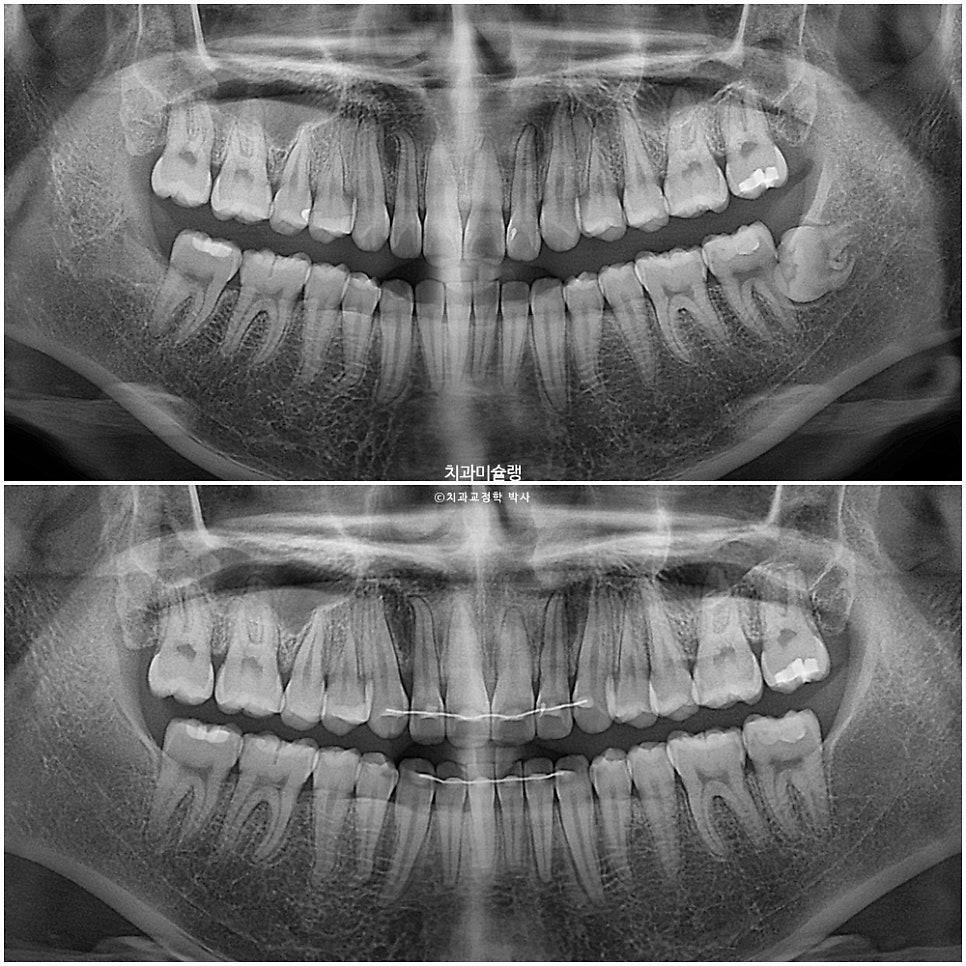

본원에 과거 4월 교정 전 엑스레이 자료가 있어 현재 11월 상태와 객관적으로 중첩을 해보았습니다.

까만선이 24년 4월 초진, 빨간선이 24년 11월 입니다.

2급 고무줄을 끼면서 위 앞니와 어금니를 포함한 전체치열이 뒤로 소량 들어가고 아래 전체치열은 앞으로 소량 나온것이 확인됩니다.

과개교합이라도 먼저 해결을 한 후 2급 고무줄을 꼈다면 모를까, 과개교합 개선이 안된 상태에서 이러한 치아이동은 앞니에 더 심한 교합간섭을 만들고 다물때 아래턱이 뒤로 밀리는 증상이 생길 수 밖에 없죠. 아래턱이 뒤로 밀리면 관절공간을 압박하여 턱관절 통증이 생길 수 있습니다.

1년 2개월간 치근흡수는 없으며, 치근평행도는 양호합니다. 사랑니 공간으로 어금니들이 잘 이동하였습니다.